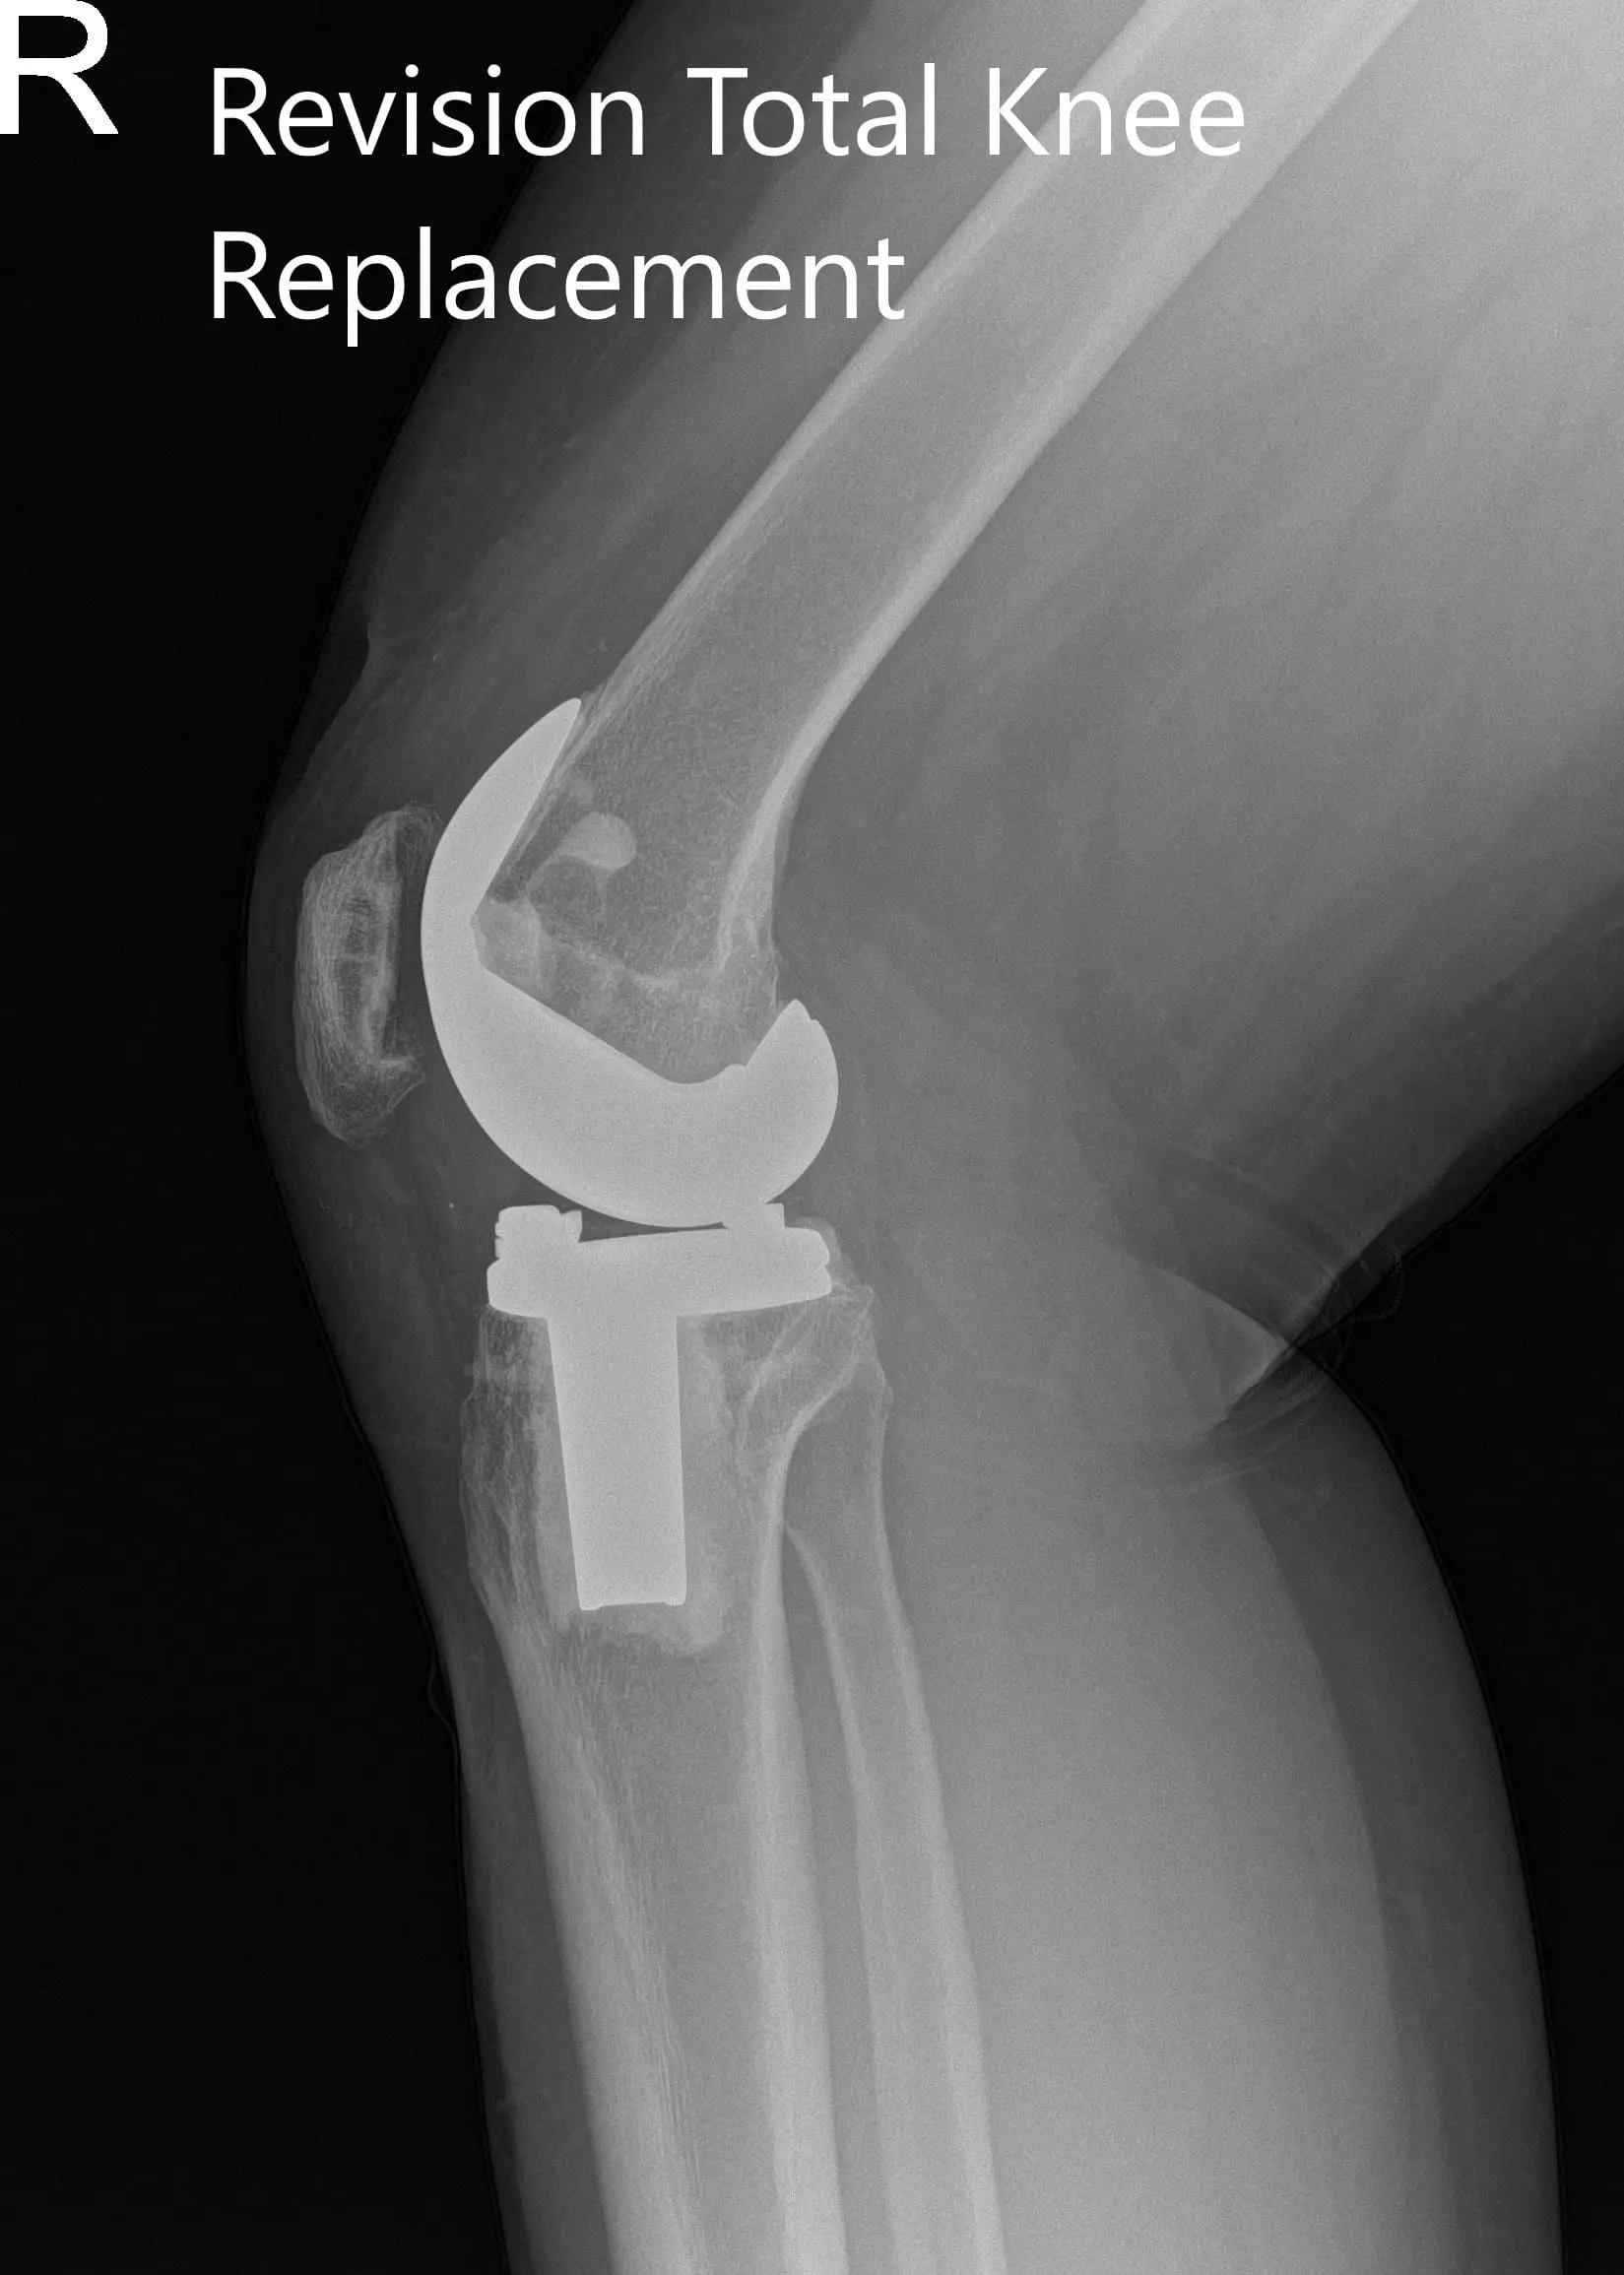

Preoperative x-ray showing the anteroposterior and lateral views of the right knee

PREOPERATIVE DIAGNOSIS(ES): Failed Right knee unicondylar knee replacement.

Postoperative x-ray showing the anteroposterior and lateral views of the right knee.